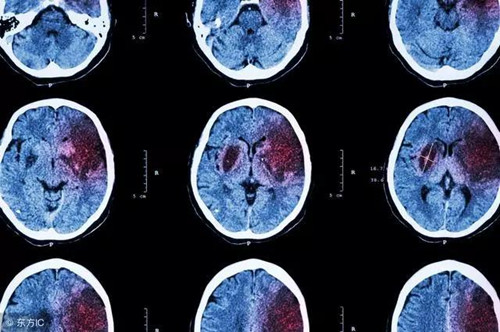

脑梗死和脑溢血都属于脑卒中,都是情况危急的脑血管病变。我国每年有150万到200万的新发脑卒中病例,其中70%是脑梗死,20%-30%为脑溢血。

脑梗死,说白了就是某个脑血管被堵塞了,使得受该血管供血的脑组织迅速坏死,治疗后多会留下偏瘫的问题。脑溢血则是某个脑血管被血流冲破,但脑组织还能获得部分供血,因而症状相对较轻,治疗后也多能完全康复。